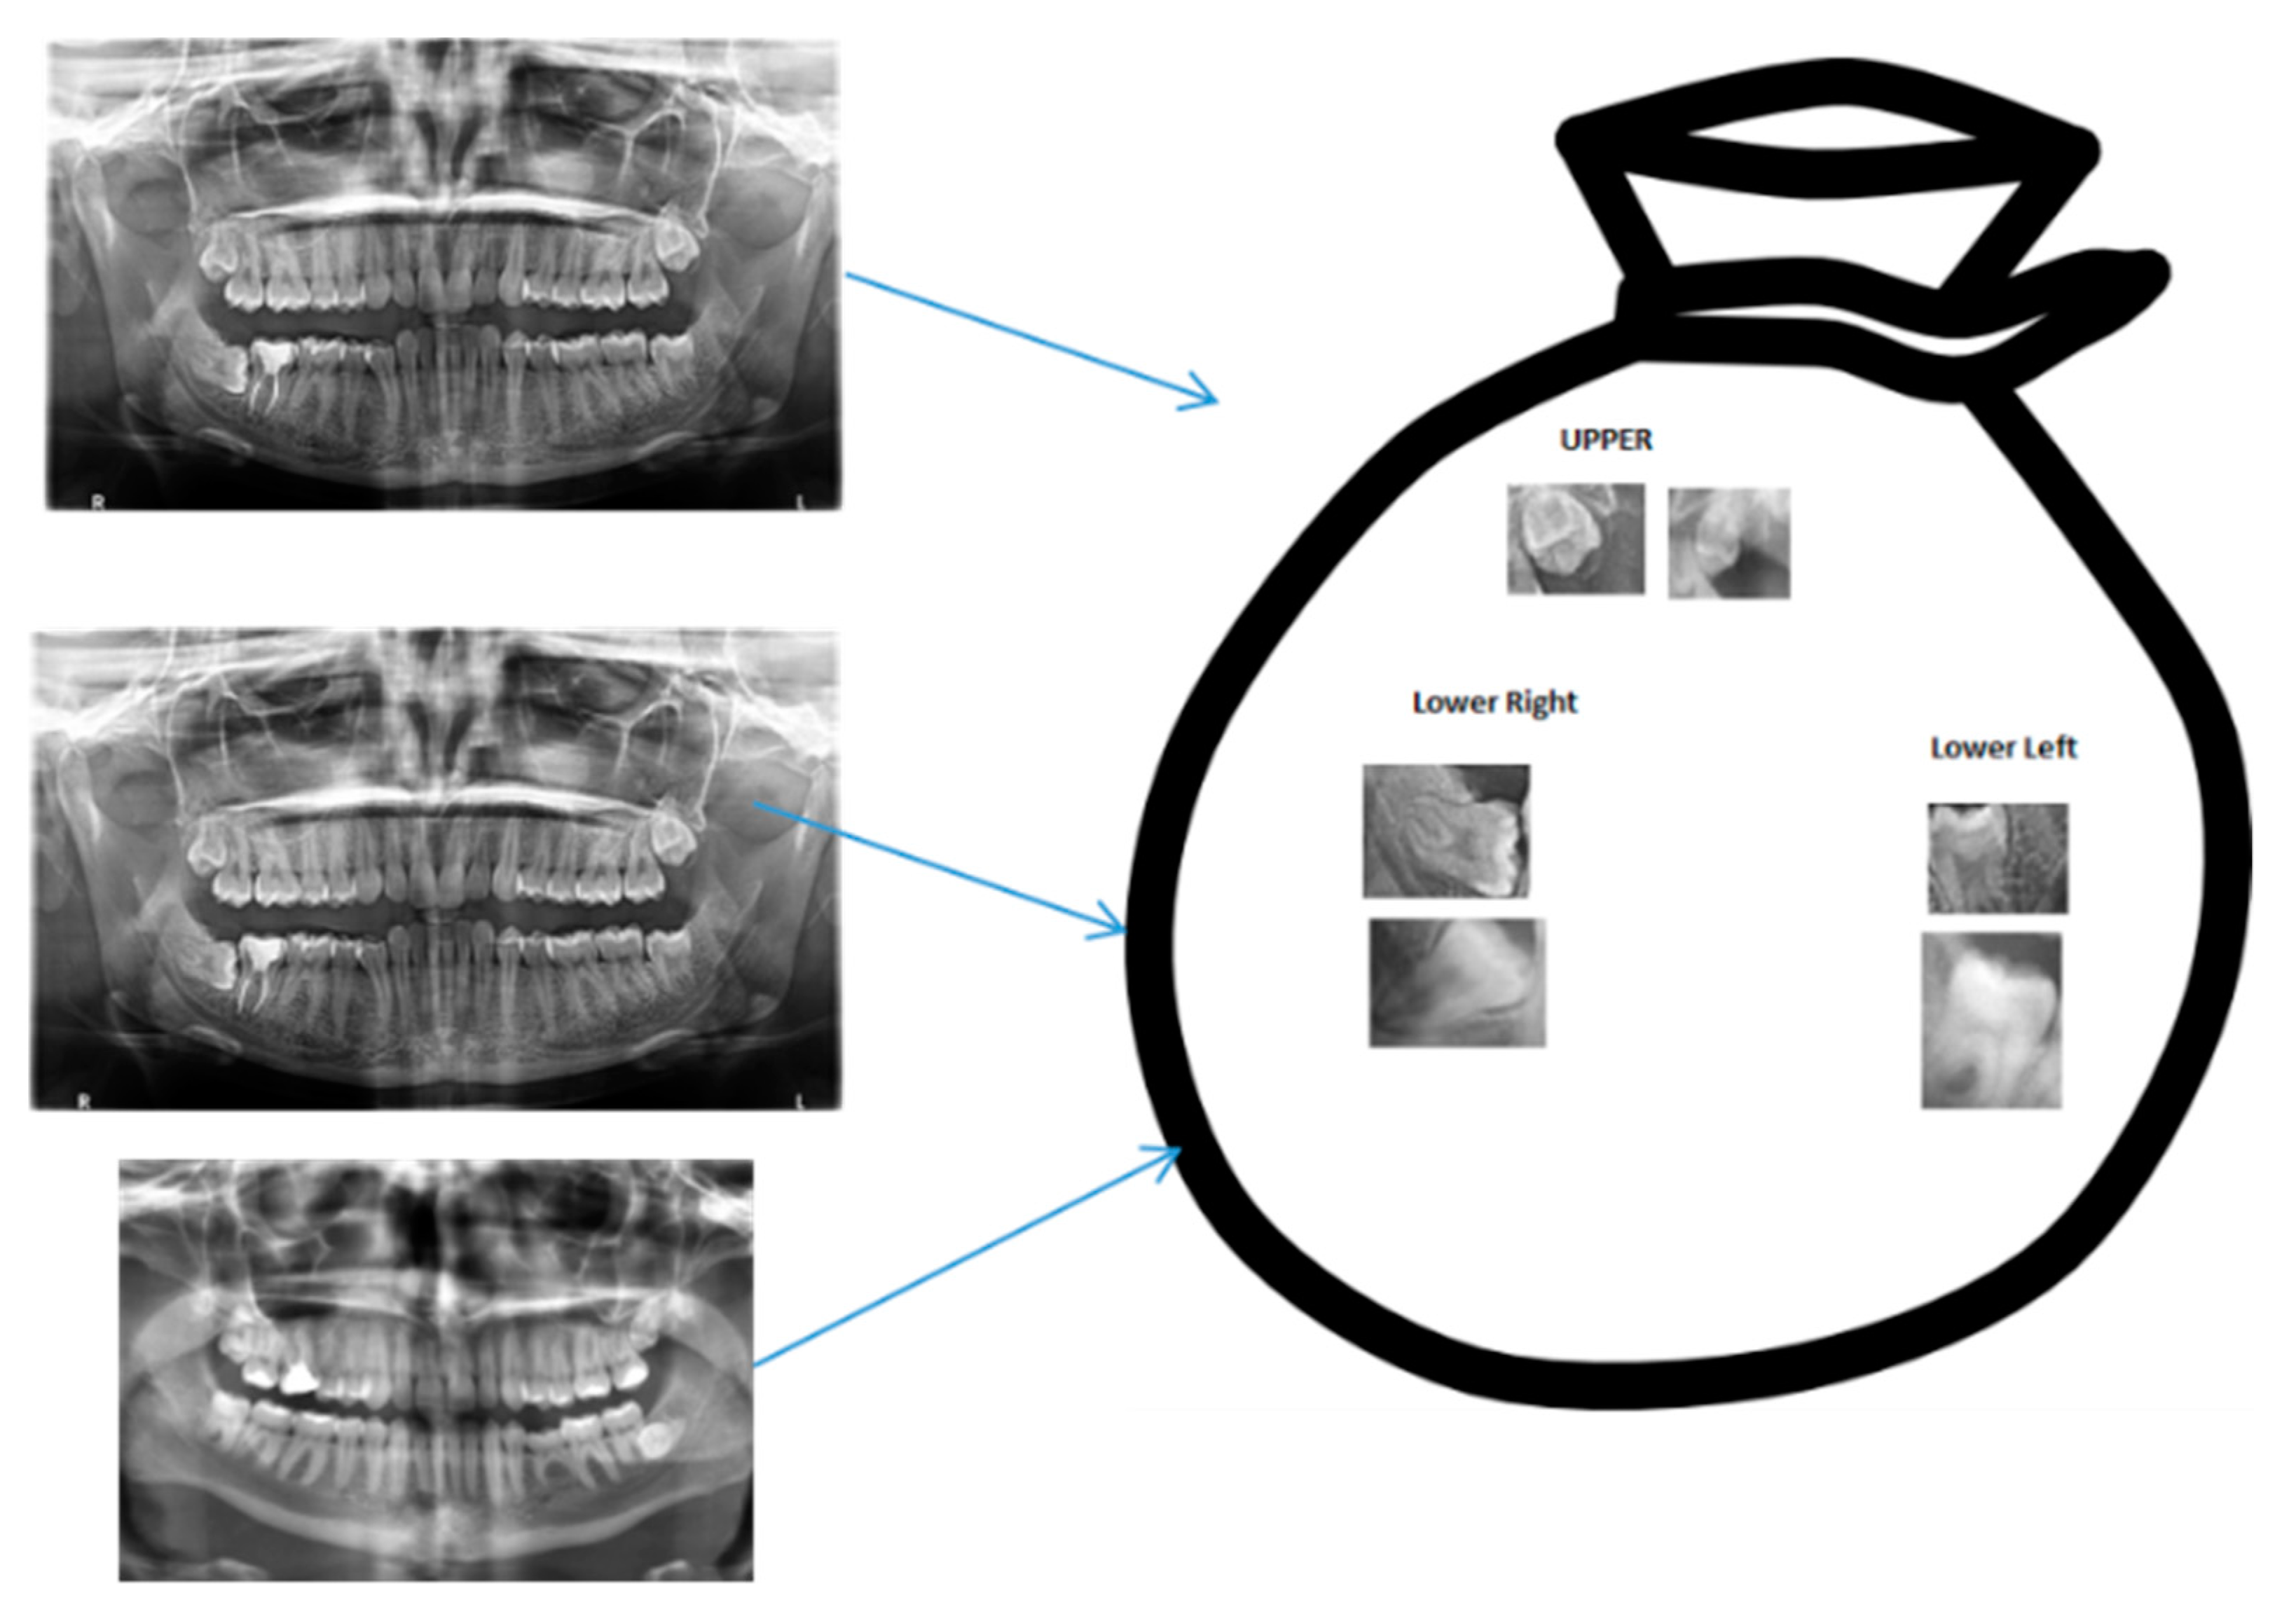

2.2.5. Bag of Visual Words